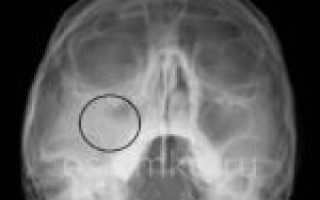

На этой фотографии отчетливо видно количество жидкости в верхнечелюстных синусах. Медики называют этот рентгеновский эффект «молоко в стакане».

У больного обнаружен гайморит с обеих сторон. Чтобы убедиться в правильности диагноза, проводится рентген в двух проекциях: прямой и боковой. Если на обоих изображениях виден уровень накопившейся жидкости, то диагноз гайморита не подлежит сомнению.

Если на изображении, помимо уровня жидкости, обнаруживаются круглые затемнения в верхней части синуса, это может свидетельствовать о возможном появлении новообразований, таких как кисты, опухоли или полипы. В таких случаях проводится контрастная рентгенография, компьютерная томография с пошаговыми срезами и другие методы исследования, которые помогут определить природу новообразований.

Почти всегда при гайморите на рентгене (фото 6) обнаруживается характерное изображение, напоминающее молоко в стакане: в черных пазухах видно белое инфильтративное содержимое. Рентгеновский снимок пазух носа при гайморите, в сочетании с диагностическими симптомами, помогает врачу поставить правильный диагноз. Однако при скоплении гноя при гайморите (фото внизу страницы), патологические тени округлой формы не наблюдаются.